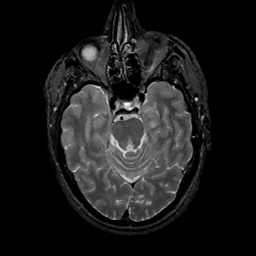

MR Study #11, May 5, 1991 -- Slice #17

[Home][Help][Clinical][Tour 1][Tour 2] Slice 17